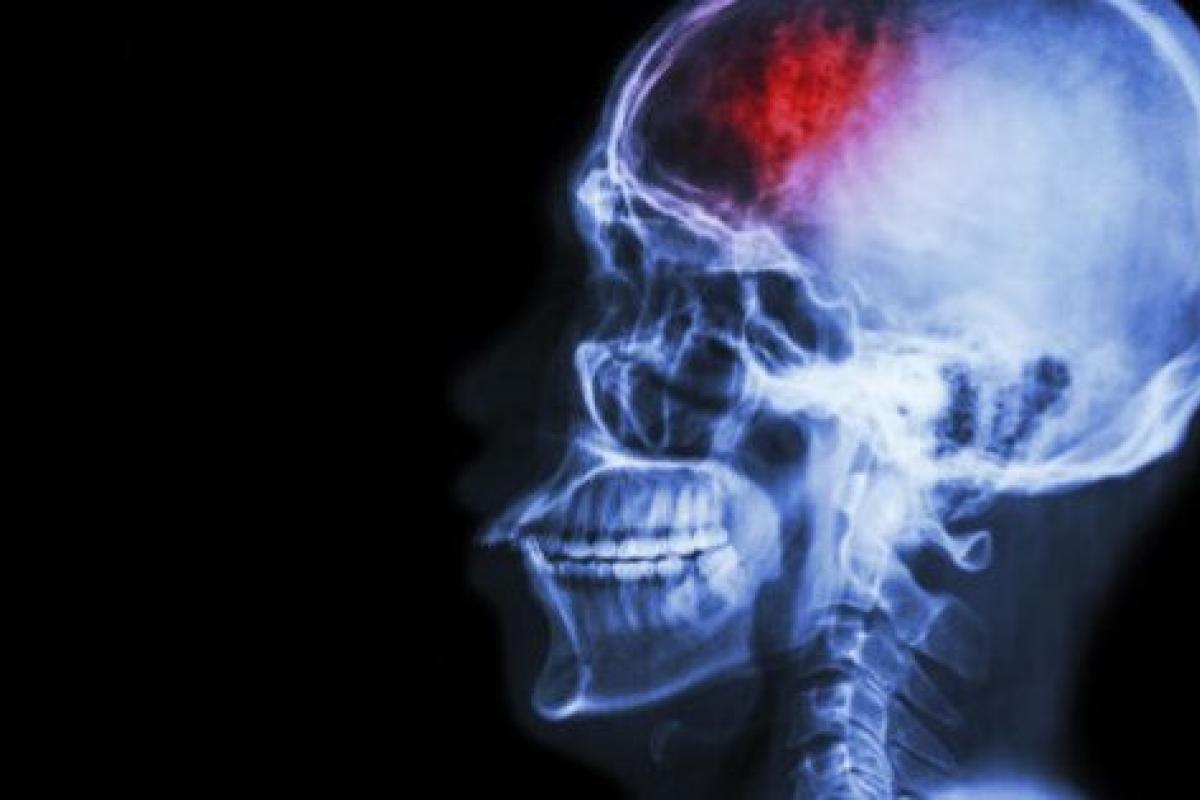

Los autores han hallado que la amígdala de nuestro cerebro —la que se encarga del procesamiento y almacenamiento de reacciones emocionales— se activa cuando mentimos para lograr un beneficio, pero también que la respuesta de la amígdala es menor con cada mentira que pronunciamos.